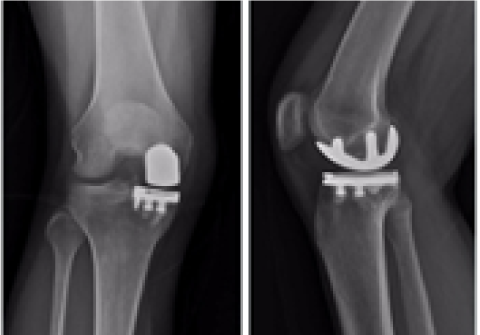

무릎 인공관절 부분치환술

2016.06.27

2016.12.28